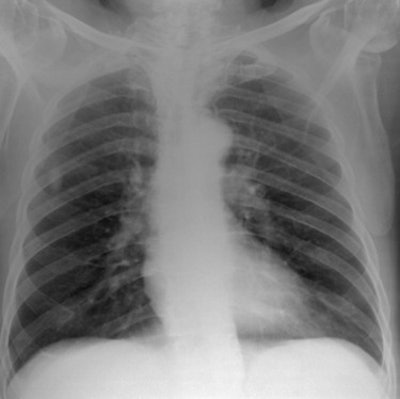

Moore and colleagues used the results of their previous optimization study of computer-simulated posteroanterior chest images (BJR, September 2012, Vol. 85:1017, pp. e630-e639) to investigate the images' correlation with the physical image quality metrics, eDE and CNR, across the diagnostic energy range (50-125 kV).

To measure clinical image quality, the researchers used results of their previously published study in which four experienced image evaluators graded computer-simulated posteroanterior chest images using a visual grading analysis scoring scheme. For physical image quality, eDE was measured in a uniform chest phantom. Correlation between the two was determined using Pearson's correlation coefficient or R.